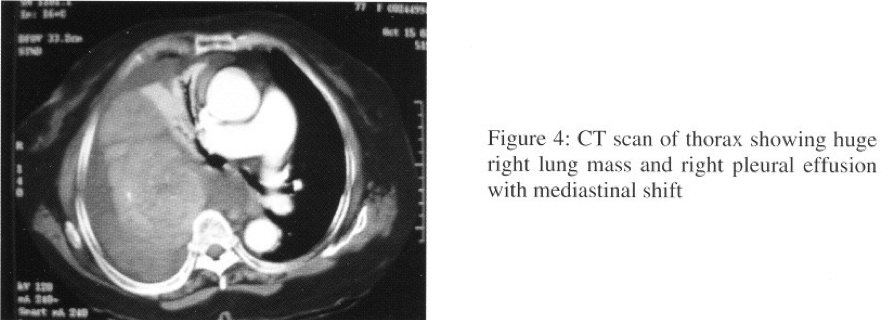

Arterial blood gases showed type I respiratory failure (pH7.44,PaC02 5.52,Pa02 7.30, HC03 27.2, Sa02 89%). Bronchoscopy showed a bulge seen over posterior segment of right upper lobe bronchus. Bronchial aspirate showed atypical cells. Transbronchial needle aspiration (TBNA) over right upper lobe bronchus was negative for malignancy. CT scan of thorax showed huge right lobulated lung mass with heterogeneous intra-lesional contrast enhancement and significant mass effect with displacement of the mediastinum towards left side and collapsed right upper, middle and lower lobes. Right sided pleural effusion was also present (Figure 4). The radiological feature was suggestive of mesothelioma, with differential diagnosis included other sarcoma.

SFT appears as a sharply delineated, sometimes lobulated mass with same density as the musculature on CT scanning with usua1ly homogeneous contrast enhancement due to rich vascularization. However non-enhancing areas can be seen due to tissue necrosis, myxoid degeneration, or haemorrhage within the tumour. Contact with the pleural surface and displacement or invasion of the adjacent structure are the characteristic features of SFT on CT scan. MRI study defines the extent of SFT more clearly when compared with CT scanning and provides better tissue characterization. Both benign and malignant SFT have low signal intensity on TI -weighted images; while on T2-weighted images, benign SFT has a low intensity whereas malignant SFT appears with high signal intensity (due to increased vascularity, oedema and ce1lularity).